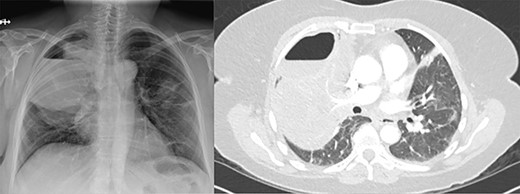

At the time of transfer, the patient was afebrile and hemodynamically normal, and she was not requiring supplemental oxygen. Her C-reactive protein level was 14.86 mg/l (reference <10) and white blood cell count was 8800 per mm3 (reference 4.5–10). Prior to transfer, her C-reactive protein level had been within normal limits. Computed tomography (CT) of the chest showed a residual pneumothorax (Fig. 2) and peripheral bronchopleural fistula (BPF). We treated her with open thoracostomy drainage (Clagett procedure), removing a segment of the second rib and suturing skin flaps to the thickened parietal pleura (Fig. 3). Due to institutional policy, no intra-operative images were obtained. On direct visualization, the visceral pleura overlying the upper lobe was thickened, but no frank purulence was noted. There was fibrinous exudate and air leak at two sites on the surface of the lung. A sample of the fibrinous tissue was sent to microbiology for clinical culture, which subsequently grew MSSA.

Axial image demonstrating right upper lobe consolidation and residual pneumothorax despite tube thoracostomy.